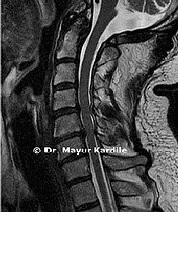

Cervical Spinal Cord Decompression

Cervical Laminoplasty

Cervical Laminoplasty relieves compression on the spinal cord in the neck by expanding the spinal canal.